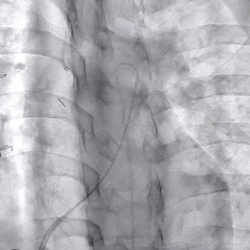

术前造影(可见大量反流)

术后造影(无反流)